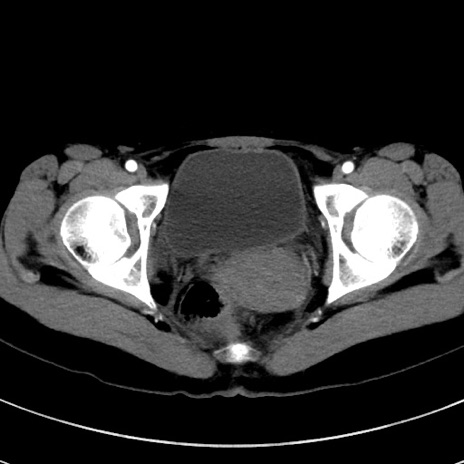

症例17(横断像)

【症例】20歳代女性

【主訴】嘔吐、下腹部痛

【現病歴】昨日夕食後に嘔吐し下腹部痛が出現。本日になっても嘔吐持続し改善しないため来院。

【身体所見】意識清明、BT 37.2℃、BP 108/67mmHg、腹部:平坦、やや硬、下腹部正中から右にかけて圧痛あり、反跳痛軽度あり、tapping pain(+)。

【データ】WBC 13600、CRP 14.94